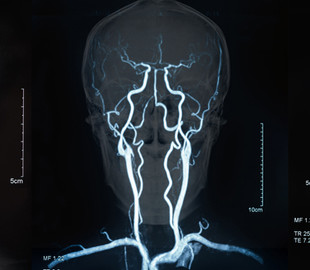

Программа HemoSYS использует фундаментальные инженерные принципы для анализа и интеграции различных видов данных, собранных различными методами визуализации. Эти данные позволяют ученым строго картировать весь «гемодинамический ландшафт» изучаемой опухоли. Результатом является красочная, но информативная визуализация, которая показывает взаимосвязь между кровотоком, оксигенацией и опухолевыми клетками в ярких красных, синих и зеленых тонах.

Система позволяет врачам увидеть, что в опухоли может быть область с низким содержанием кислорода, вызванным плохим кровотоком, или увидеть, что в области мало кислорода, хотя в ней наблюдается повышенный объем крови. Программу можно адаптировать к взаимодействию с другими методами визуализации — таких как МРТ, УЗИ и динамическая КТ.